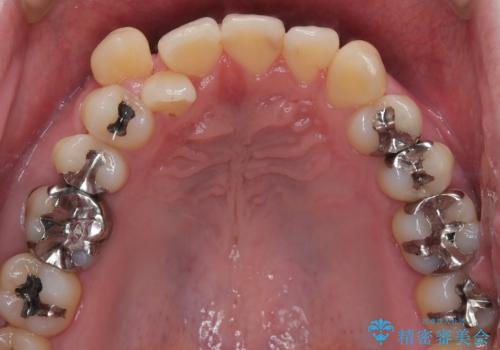

- 右上2番目の歯が舌側転位していることと前歯の叢生(がたつき)を主訴に来院されました。

右上の犬歯が初診時よりかなり歯根露出しており、矯正の力をかけるとさらに歯根露出するリスクがあるため、右上の2番目の歯を前に出すためにも

右上の犬歯を抜歯して歯並びを整える治療計画を立てました。

下のがたつきをとるために、IPR(歯と歯の間を削る処置)も行って歯を並べていきます。